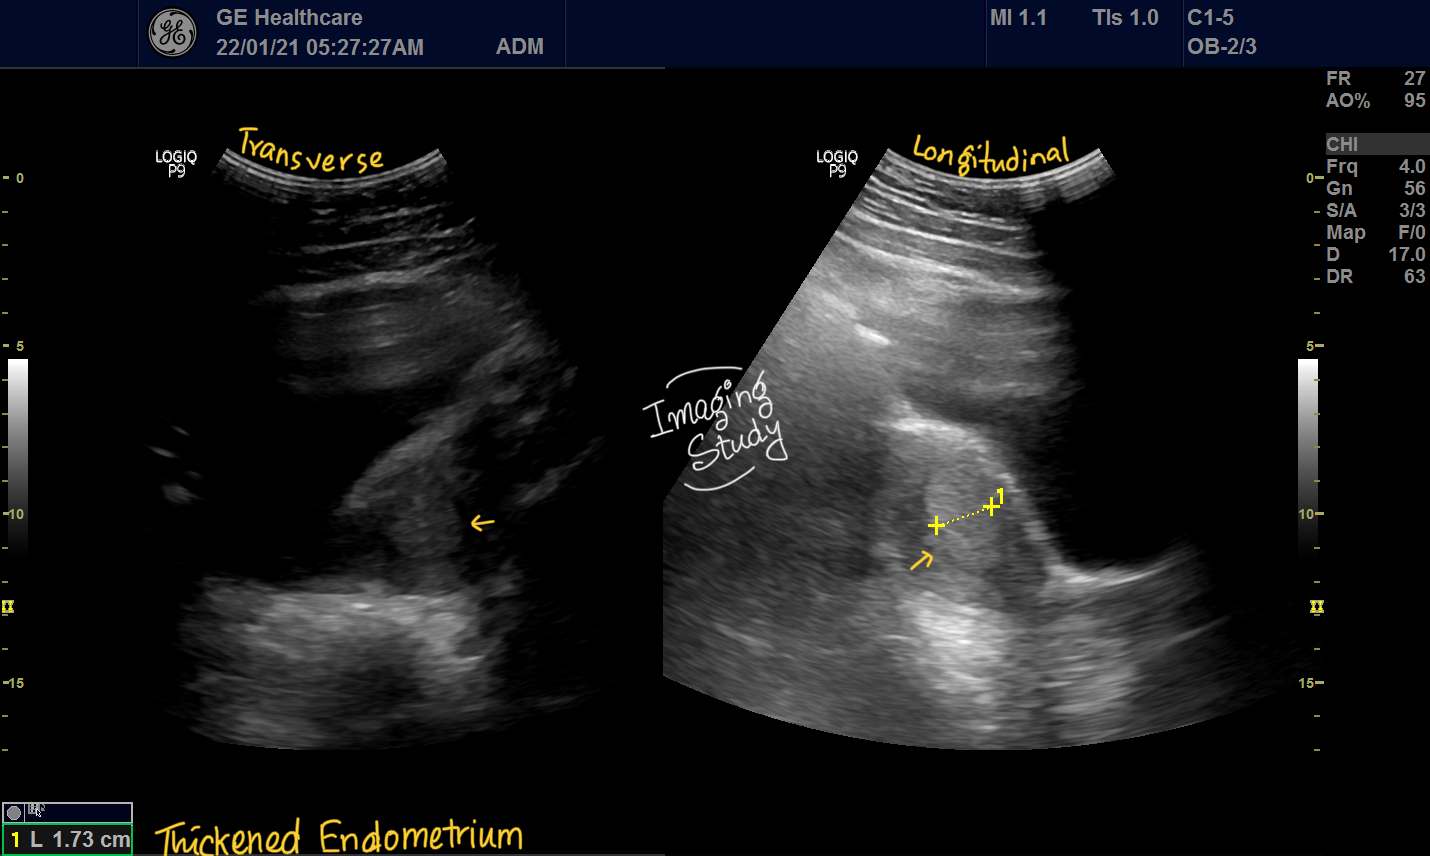

From www.imagingstudy.com

Case 26 Thickened Endometrium Imaging Study Thickened Endometrium After D&C A dilation and curettage (d&c) is a procedure to remove tissue from your uterus. Used for both treatment and diagnosis, dilation and curettage surgery, commonly referred to as d&c, is a procedure. A dilation and curettage (d&c) is a procedure to remove tissue from your uterus. Atypical endometrial hyperplasia raises your. The condition is associated with heavy. It can cause. Thickened Endometrium After D&C.